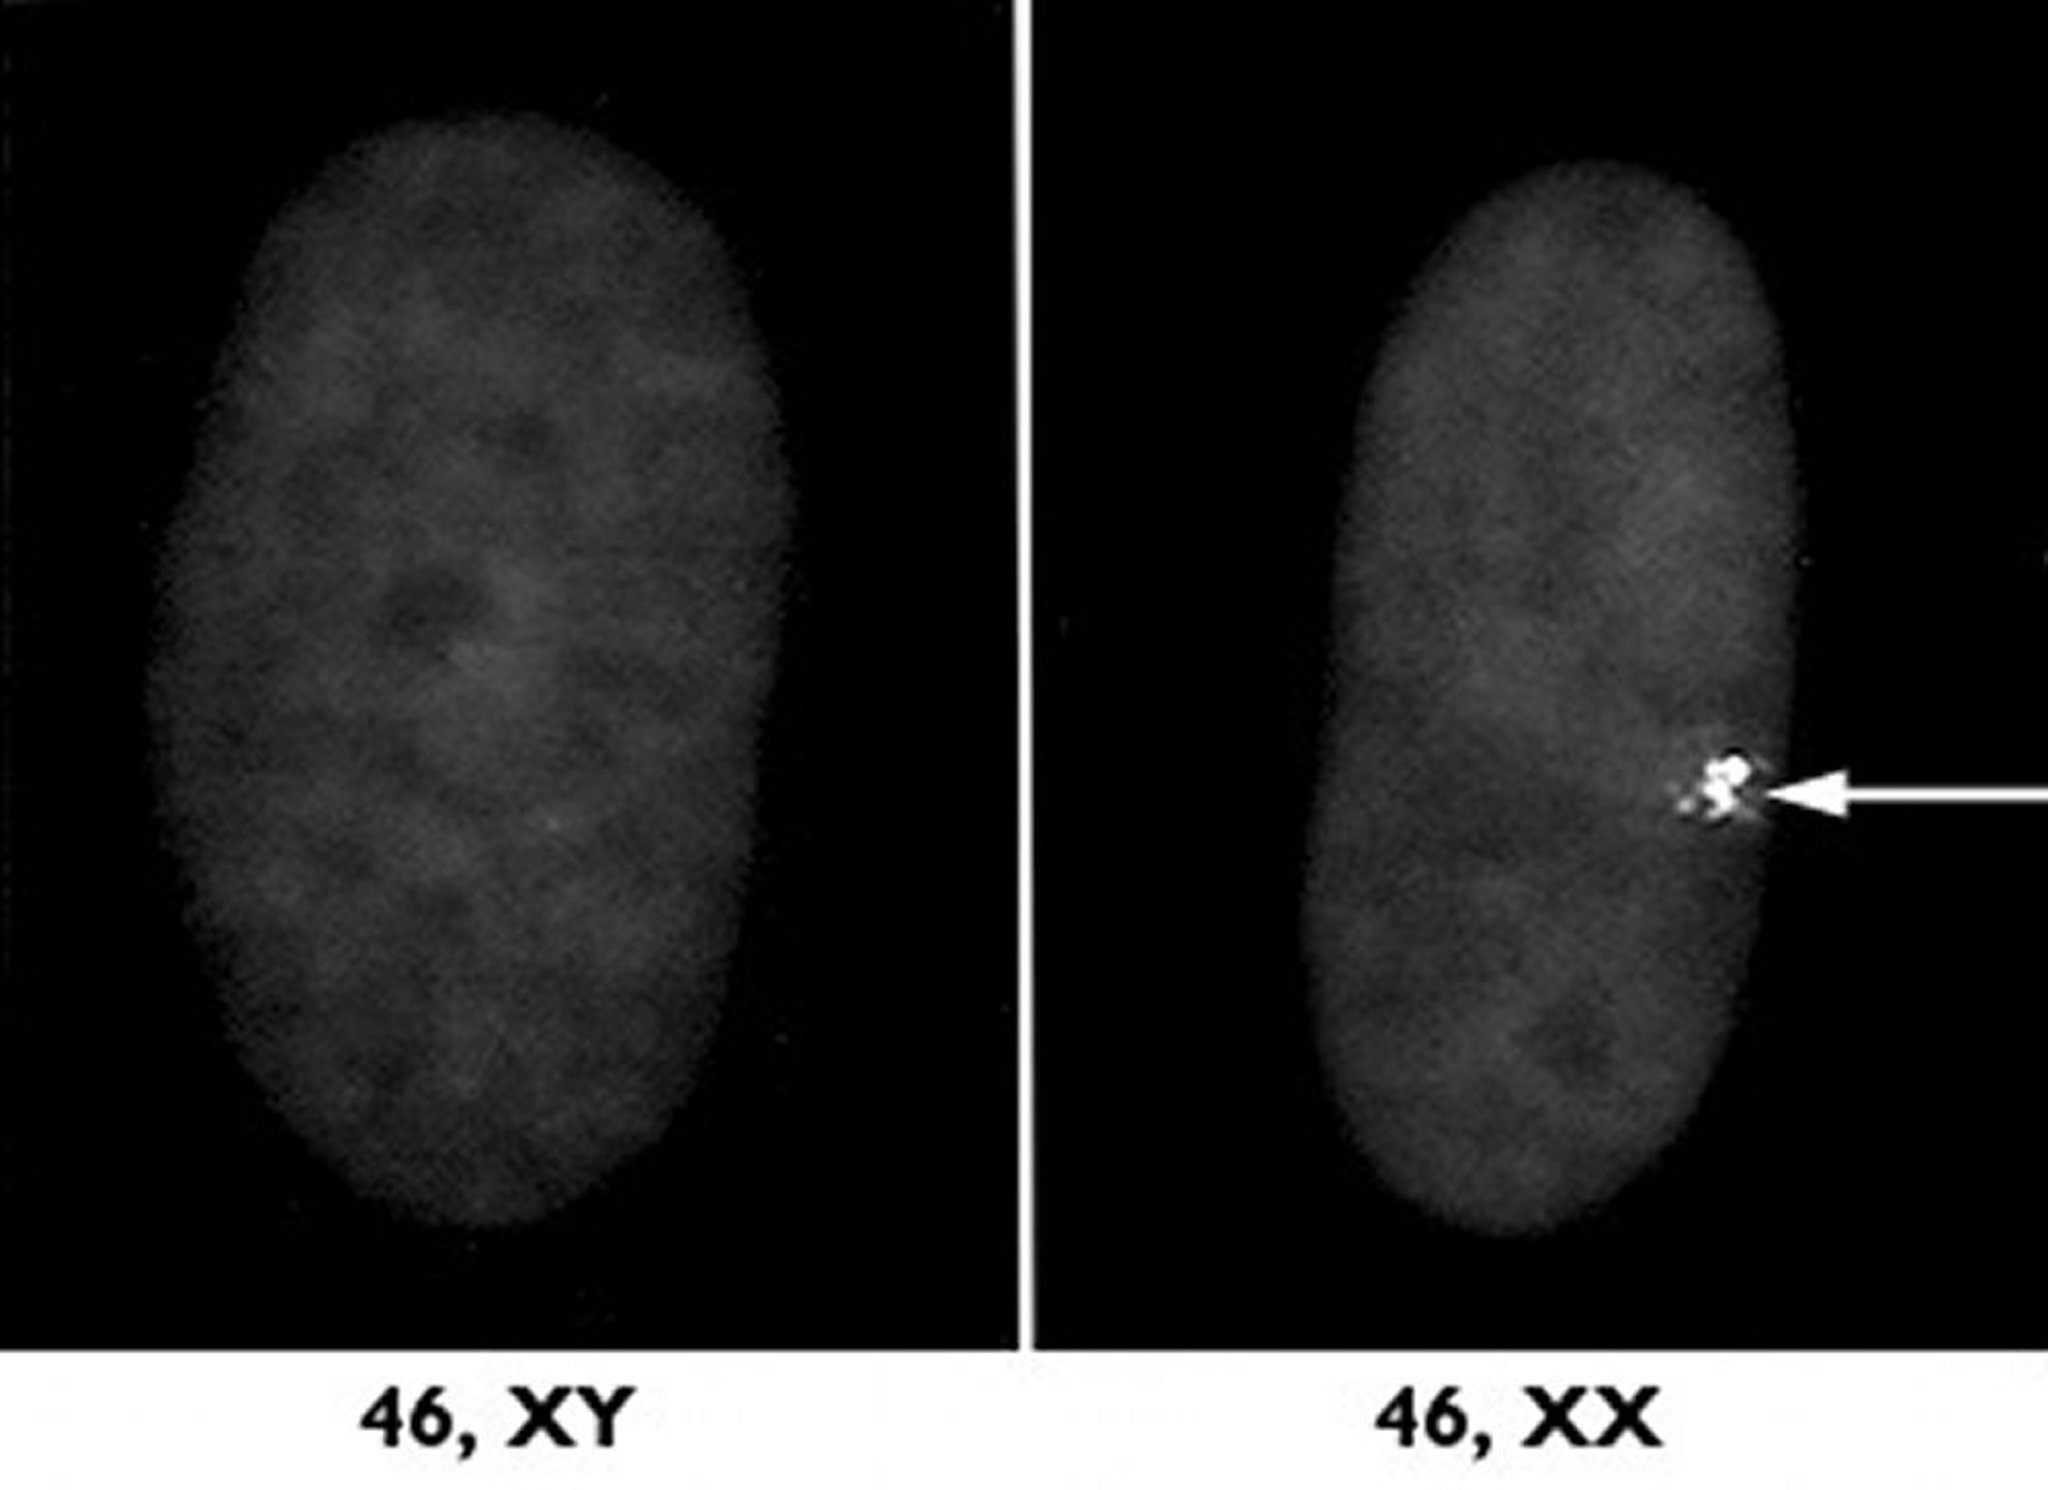

Inactivation du chromosome X

L’un des deux chromosomes X des femmes ne fonctionne pas en raison d’un processus appelé inactivation du chromosome X. À droite, le chromosome X inactivé est visible à partir d’un échantillon microscopique de noyau cellulaire provenant d’une femme, sous la forme d’une masse dense (flèche). À gauche, un échantillon provenant d’un homme est présenté pour la comparaison.

Avec l’aimable autorisation des Drs L. Carrell et H. Williard, Case Western Reserve University School of Medicine.